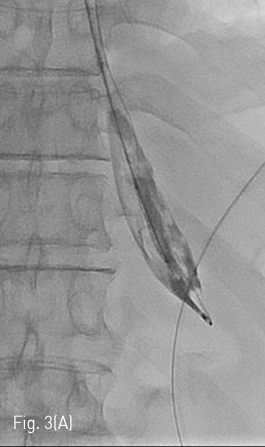

Fig 3A

(A) J-tip guidewire is inserted so that the tip of it was retained within the ruptured balloon. The ruptured balloon is then advanced along with 0.035 inch guidewire into the stomach.